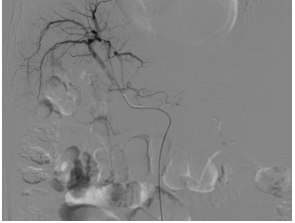

栓塞后瘤体染色基本消失